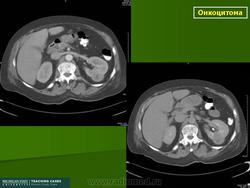

Почечная онкоцитома

Почечная онкоцитома.